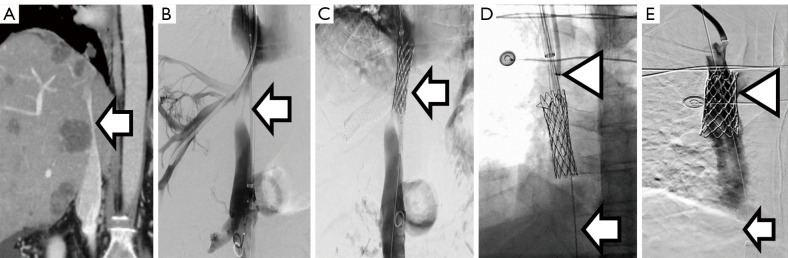

Abstract Image